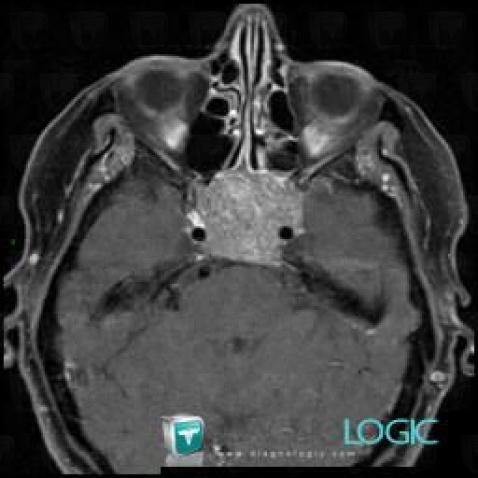

Macroadénome hypophysaire, Hypophyse et région parasellaire, IRM

Voici les informations spécifiques à l'image clé ci dessus:

- Diagnostic Macroadénome hypophysaire, Localisation(s) Hypophyse et région parasellaire, comportant les gammes Lésion du sinus caverneux